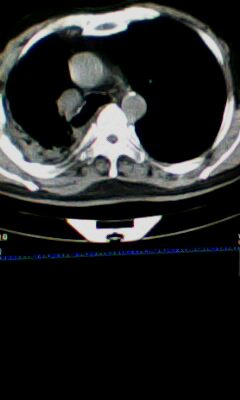

标题: CT25675:男 71 肺癌部分切除术后 3年 [打印本页]

标题: CT25675:男 71 肺癌部分切除术后 3年

1)两肺感染性病变。2)右侧胸膜增厚。3)冠状动脉及主动脉钙化。

1.右肺符合肿瘤切除术后ct表现。

2.左肺炎症。

术后改变,双肺内纤维索条影考虑与放疗有关。